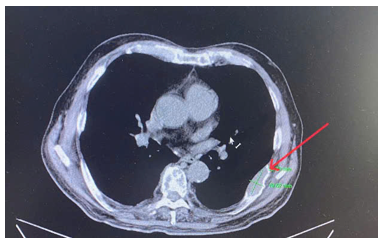

CASE LÂM SÀNG Điều trị bệnh nhân mắc đồng thời hai loại ung thư: Ung thư phổi và ung thư tuyến tiền liệt

CASE LÂM SÀNG Điều trị bệnh nhân mắc đồng thời hai loại ung thư: Ung thư phổi và ung thư...